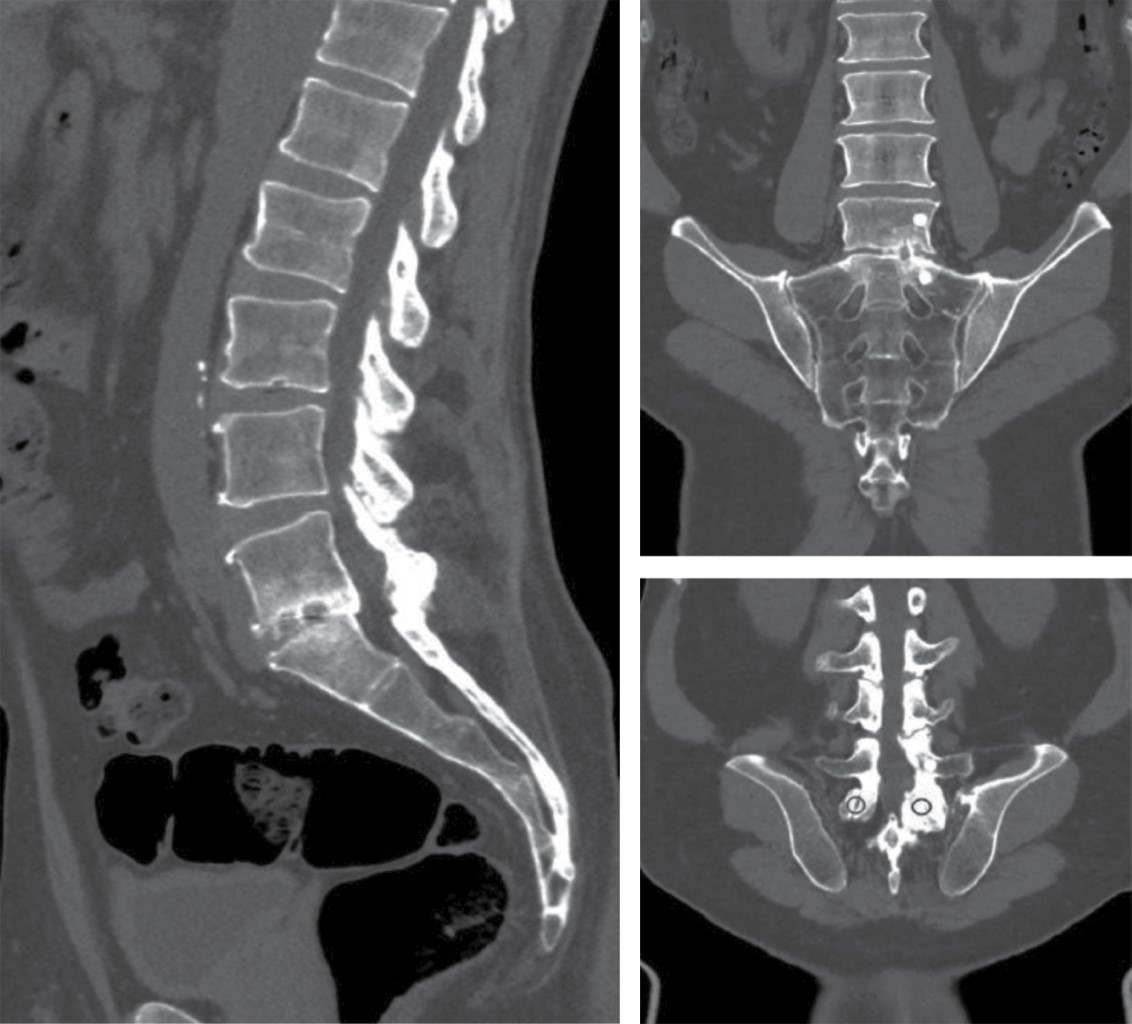

En estudio de resonancia magnética se observa degeneración discal L4-L5 grado 3 Pfirrmann, L5-S1 grado 4 Pfirrmann, presencia de hidrartrosis e hipertrofia facetaria derecha de 1 mm, protrusión discal circunferencial L4-L5, estrechamiento intervertebral L5-S1 con implante intersomático tipo banana, con erosión y hundimiento en las plataformas (Figura 2).

En tomografía lumbosacra se identifican puentes óseos intersomáticos en L5-S1, así como fusión facetaria izquierda; sin embargo, con datos de pseudoartrosis a nivel de faceta derecha, artrosis facetaria izquierda L4-L5, plataformas escleróticas, hundimiento de caja intersomática y sitios de osteólisis (Figura 3).

Figura 2

Figura 3